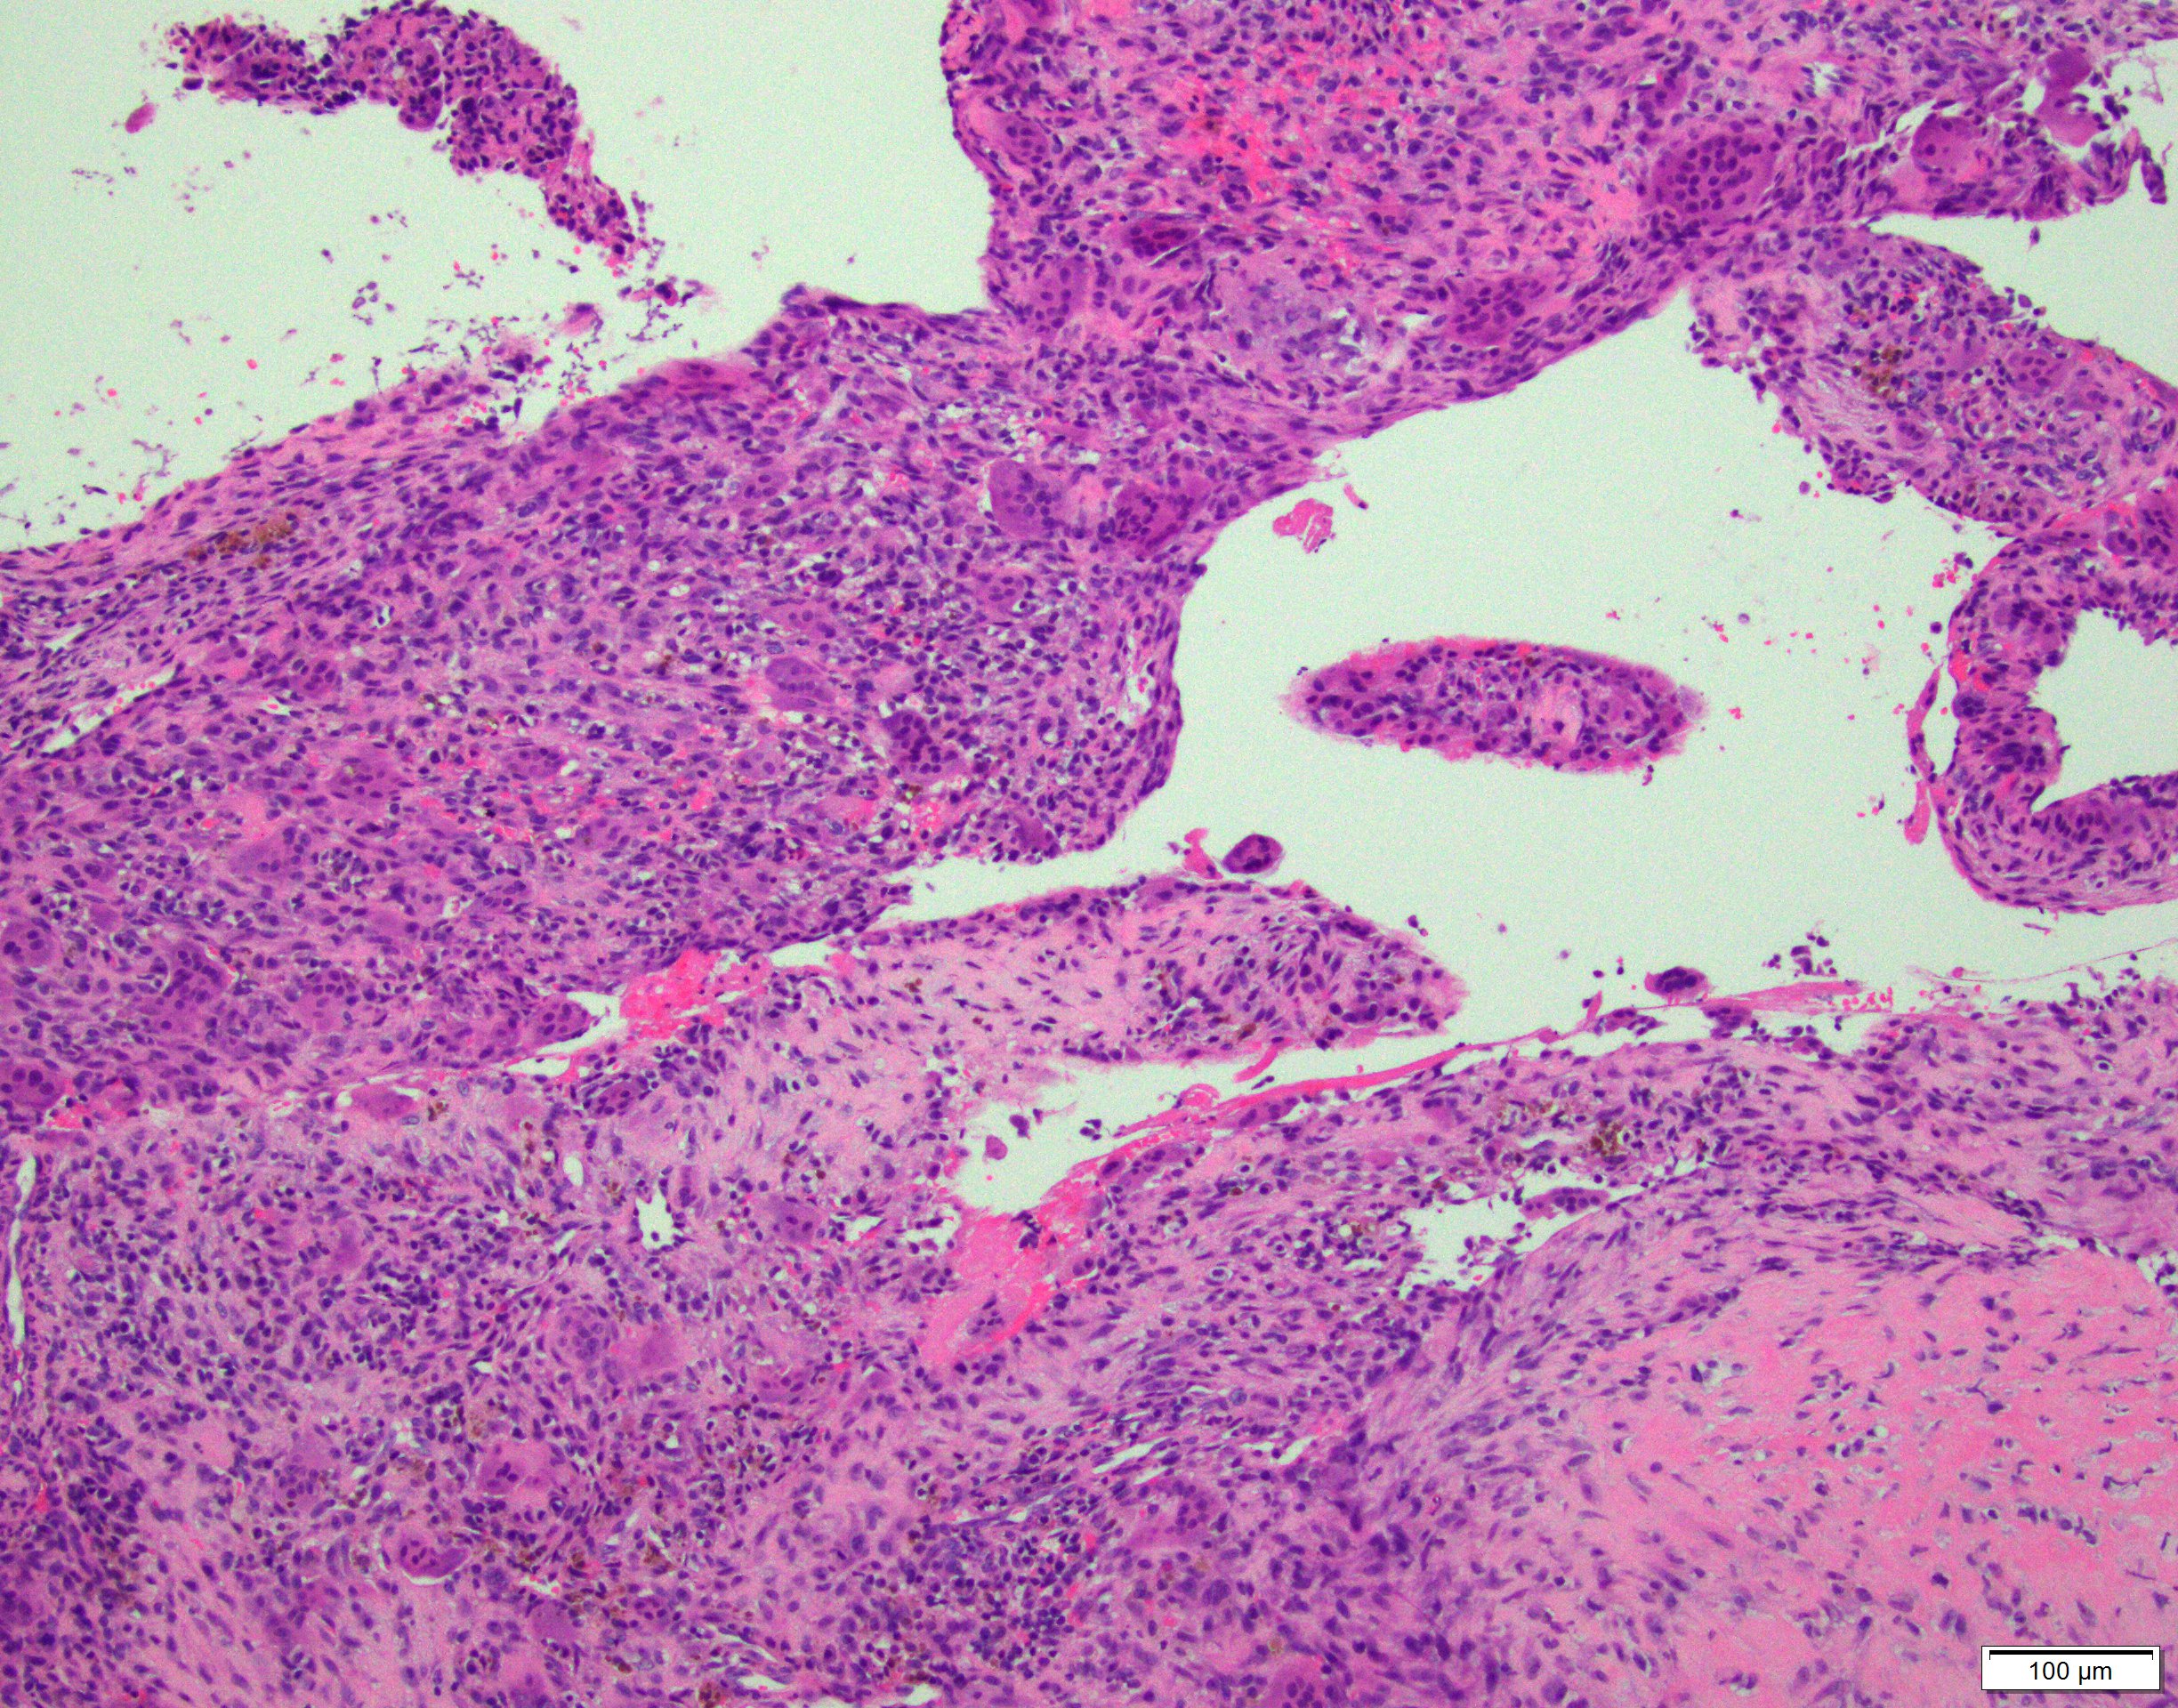

- Multiloculated cystic lesion

- Blood filled cystic spaces separated by cellular septa containing fibroblasts, giant cells and woven bone

- Calcified, basophilic material (blue reticulated chondroid-like material)

- Necrosis not common but mitotic activity is easily identified

- No cytologic atypia (Am J Clin Pathol 2015;143:823)

- Numerous giant cells in connective tissue that line large sinusoidal spaces

Microscopic (histologic) images

Contributed by Elham Nasri, M.D. and Kelly Magliocca, D.D.S., M.P.H.

A. Aneurysmal bone cyst. The H&E shows cystic spaces with stromal giant cells. Rearrangement of USP6 gene confirms the diagnosis in the above clinical and radiographic context.